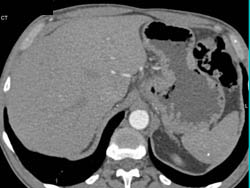

Gastric Cancer With Celiac Nodes